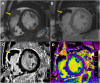

"Cases of SCMR" is a case series on the SCMR website (https://www.scmr.org) for the purpose of education. The cases reflect the clinical presentation, and the use of cardiovascular magnetic resonance (CMR) in the diagnosis and management of cardiovascular disease. The 2022 digital collection of cases are presented in this manuscript.